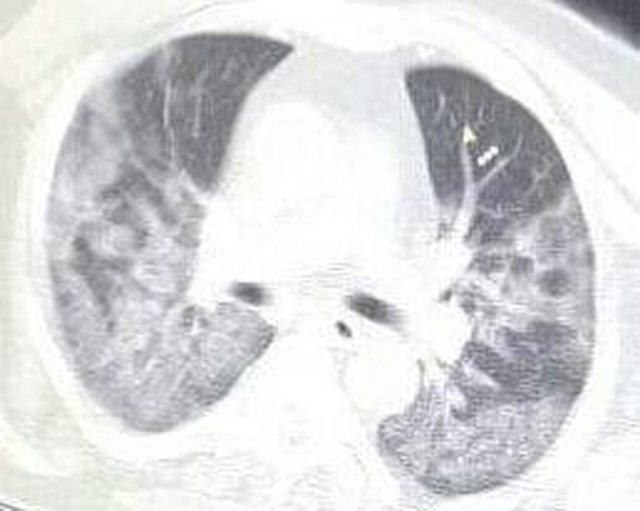

Mjeku ka kërkuar shmangien e grumbullimeve për fushatë, ndërsa ka publikuar edhe CT-Scannerave, të disa individëve të rinj që kanë humbur jetën nga covid.

“Grumbullimet në takimet elektorale, në ndodhitë familjare, në mjetet e transportit publik apo edhe në mjediset e shkollave, si edhe mungesa e zbatimit të masave të higjenës në mjediset kolektive, po ndikojnë dhe do të vijojnë të ndikojnë në shtimin e rasteve të infektimeve nga Sars-Cov2/Covid-19….FUSHATA ELEKTORALE për zgjedhjet e parlamentare të 25 Prillit 2021, për asnjë dekikë nuk duhet të zbehë përditshmërinë e punës dhe përpjekjeve në përballjen me Sars-Cov2/Covid-19….JO PËR TË FRIGUAR grup moshat nën 40-45 vjeç, por për t’i ndërgjegjësuar ato i kam bashkëngjitur këtij postimi imazhe të CT-Scannerave, të disa individëve të këtyre grupmoshave që nuk kanë mundur t’a fitojnë betejën e përballjes me këtë “flamë”….Përpiquni të qëndroni sa më larg ndikimeve jo dobiprurëse të Gjithologëve dhe Anal-istëve, që fatkeqsisht kanë mbirë kudo në TV apo në Shtypin e shkruar dhe në Rrjetet sociale…JU DUAM dhe jo pak rrezikojmë edhe jetët tona në vijën në parë, që me Punën, Përkushtimin dhe Profesionalizmin tonë të mundet në MIRËBESIM dhe MIRËKUPTIM, të ngadhnjejmë në këtë “luftë me armikun e padukshëm”….Together forever!!!”, shkruan Kalo.